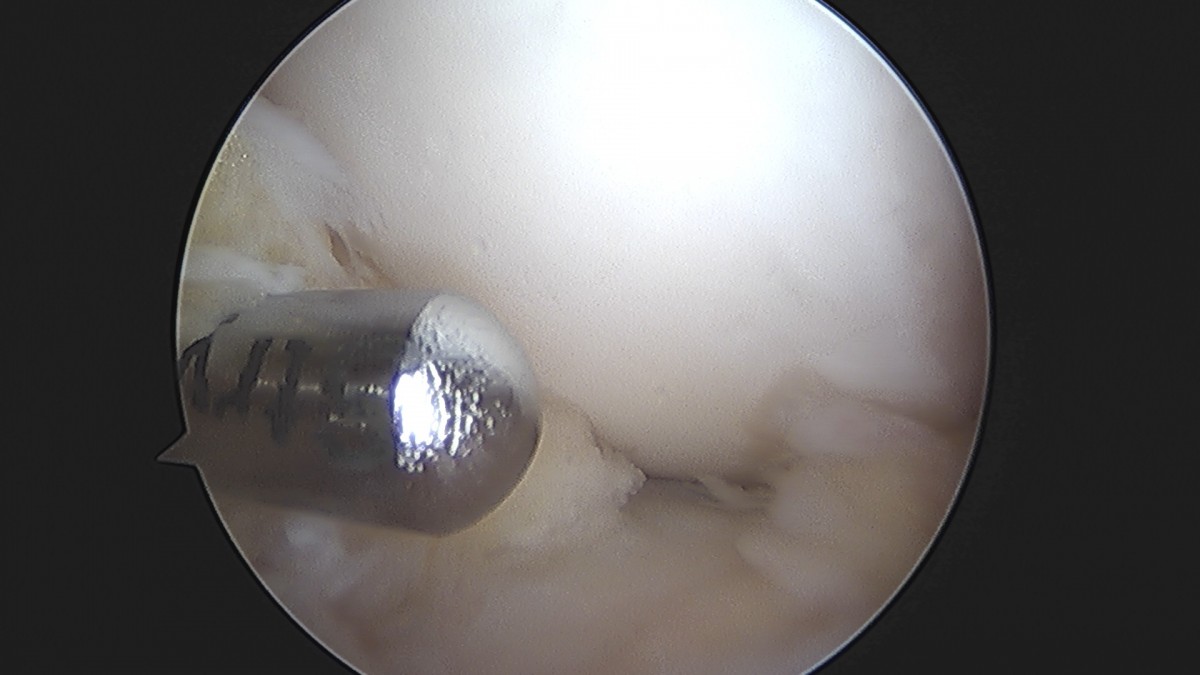

이재상원장님 무릎 반월상 연골판 절제술 장영O 환자

작성자 최고관리자 댓글 0건 조회 369회 작성일 25-09-16 16:02